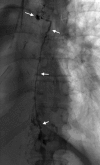

Results: Initial conservative treatment (e.g., parenteral nutrition or a special diet) succeeds in 20% to 80% of cases. When such treatment fails, the standard approach up to the present has been to treat surgically, e.g., with ligation of the thoracic duct, pleurodesis, or a pleuroperitoneal shunt. The success rates of such procedures have ranged from 25% to 95%. Most of the patients undergoing such procedures are severely ill; complication rates as high as 38% have been reported, with mortality as high as 25%. In more recent publications, however, morbidity and mortality were lower. Interventional radiological treatments, such as percutaneous thoracic duct embolization or the percutaneous destruction of lymphatic vessels, succeed in about 70% of cases and lead to healing in up to 80% of cases, even after unsuccessful surgery. The complication rate of percutaneous methods is roughly 3%.

Conclusion: Interventional radiological procedures have now taken their place alongside conservative treatment and surgery in the management of chylothorax, although they are currently available in only a small number of centers.